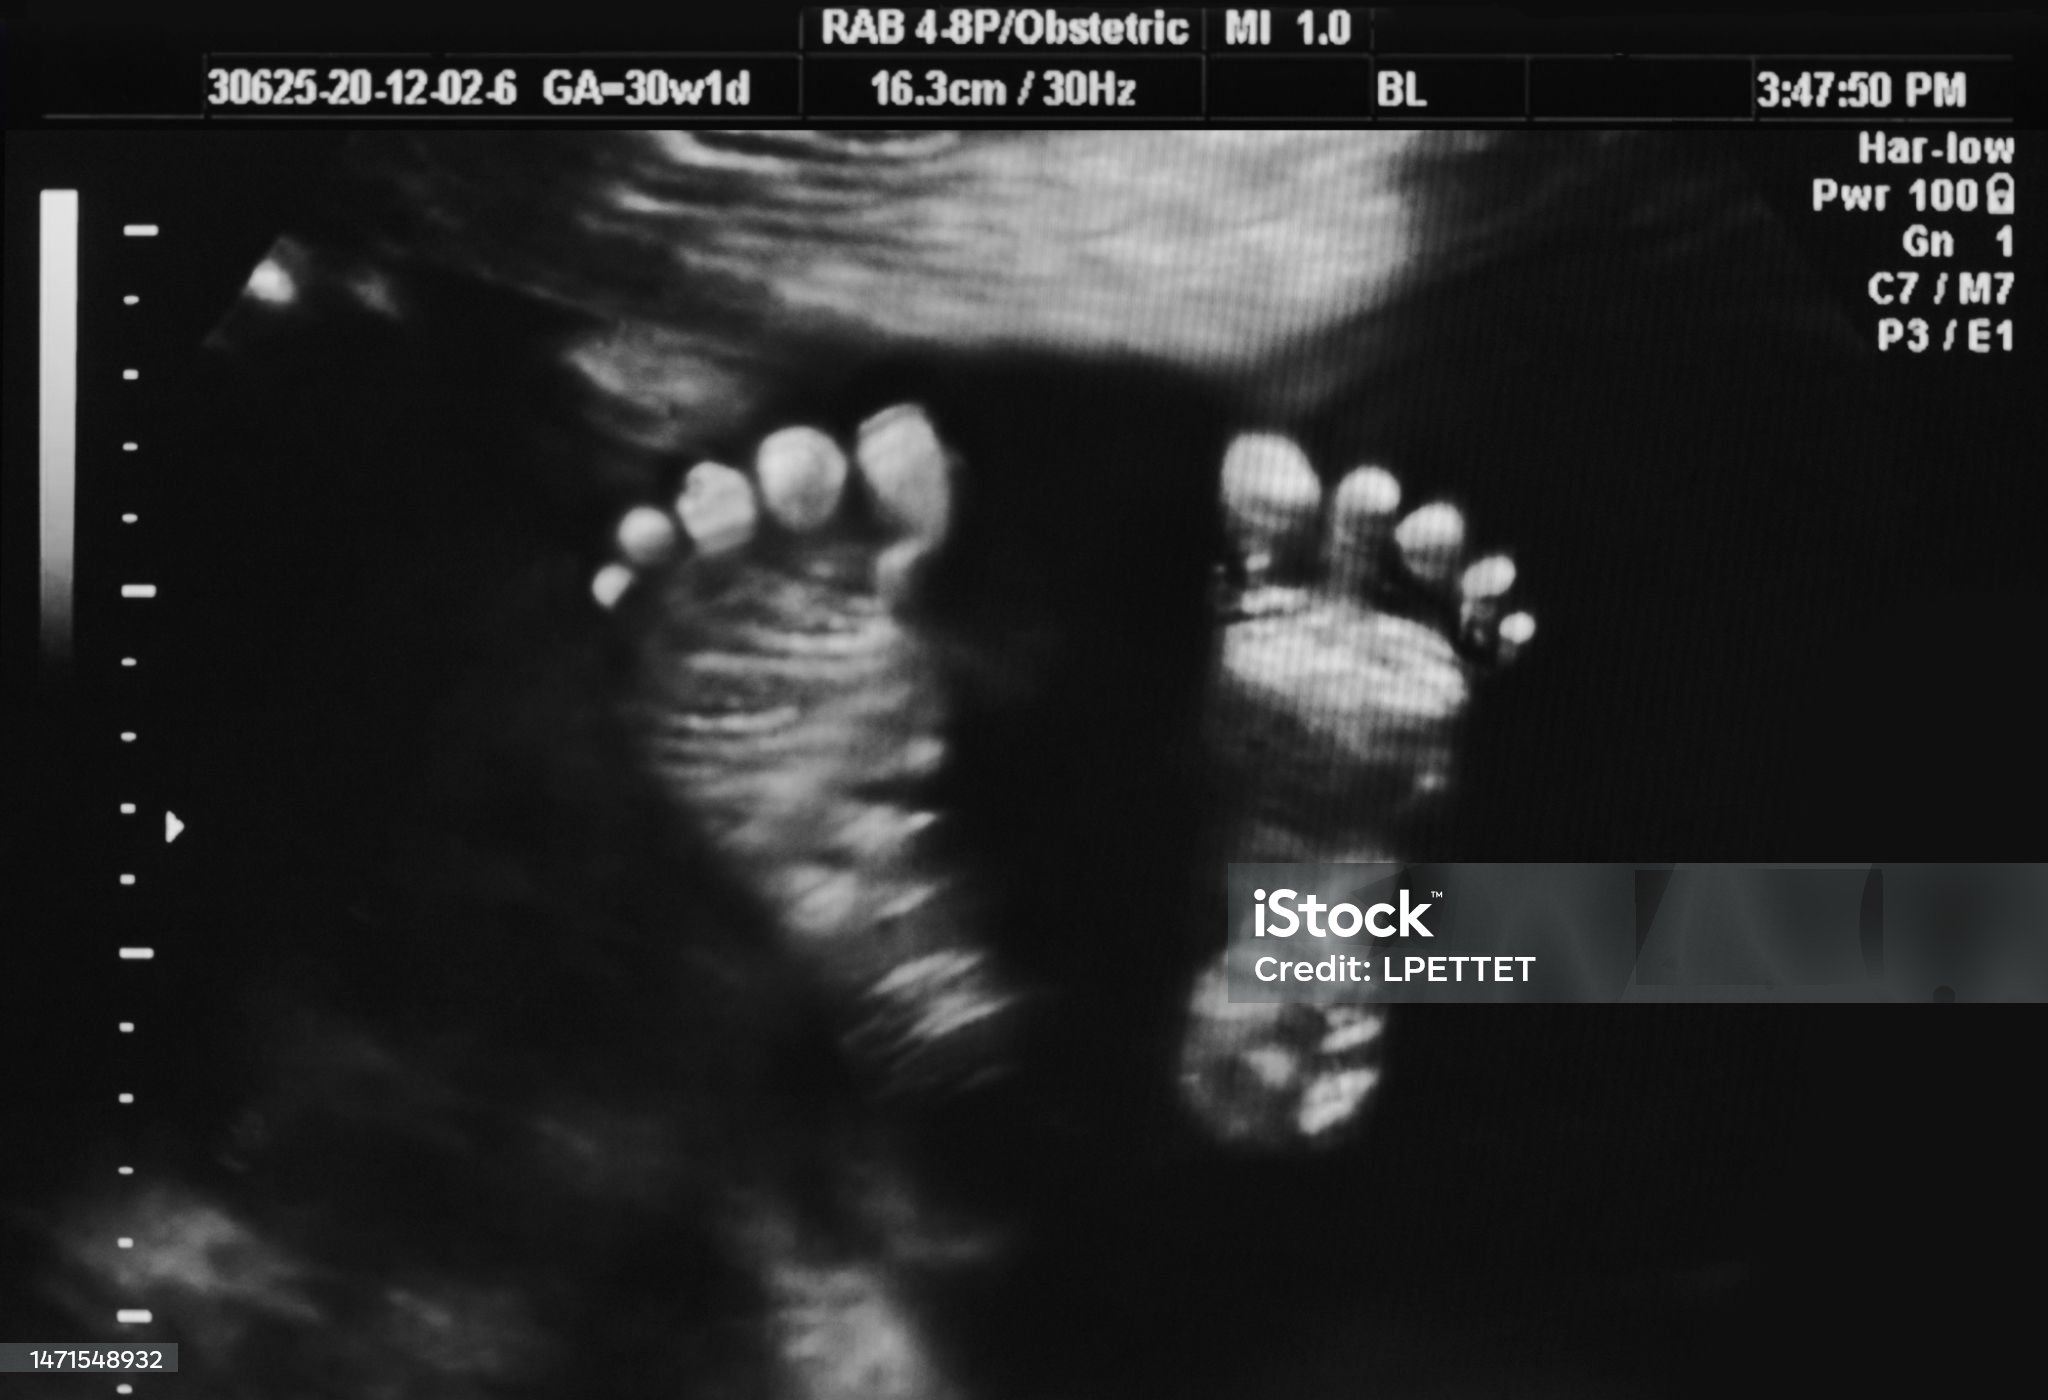

초음파 영상은 인체에 무해한 고주파 음파를 몸에 보내고, 그 음파가 조직과 장기에서 반사되어 되돌아오는 신호를 받아 이미지를 형성하는 방식입니다. 이 방법은 방사선을 사용하지 않기 때문에 임신 중 태아를 보는 데 매우 안전하며, 연조직이나 장기의 상태를 확인할 때 자주 사용됩니다.

- 임신 중 태아의 상태 확인: 초음파는 방사선 노출이 없기 때문에 임신한 여성의 태아 상태를 검사하는 데 사용됩니다.

- 초음파: 초음파는 방사선을 사용하지 않기 때문에 몸에 전혀 해를 끼치지 않으며, 임산부나 신생아도 안전하게 검사를 받을 수 있습니다. 방사선 걱정 없이 반복해서 사용할 수 있는 점도 큰 장점입니다.

- 초음파: 초음파는 실시간으로 움직이는 영상을 얻을 수 있어 태아의 상태나 심장의 움직임을 관찰할 때 유용합니다. 그러나 공기나 뼈처럼 밀도가 높은 조직은 초음파로는 잘 보이지 않기 때문에 폐나 뼈를 검사하는 데는 적합하지 않습니다.